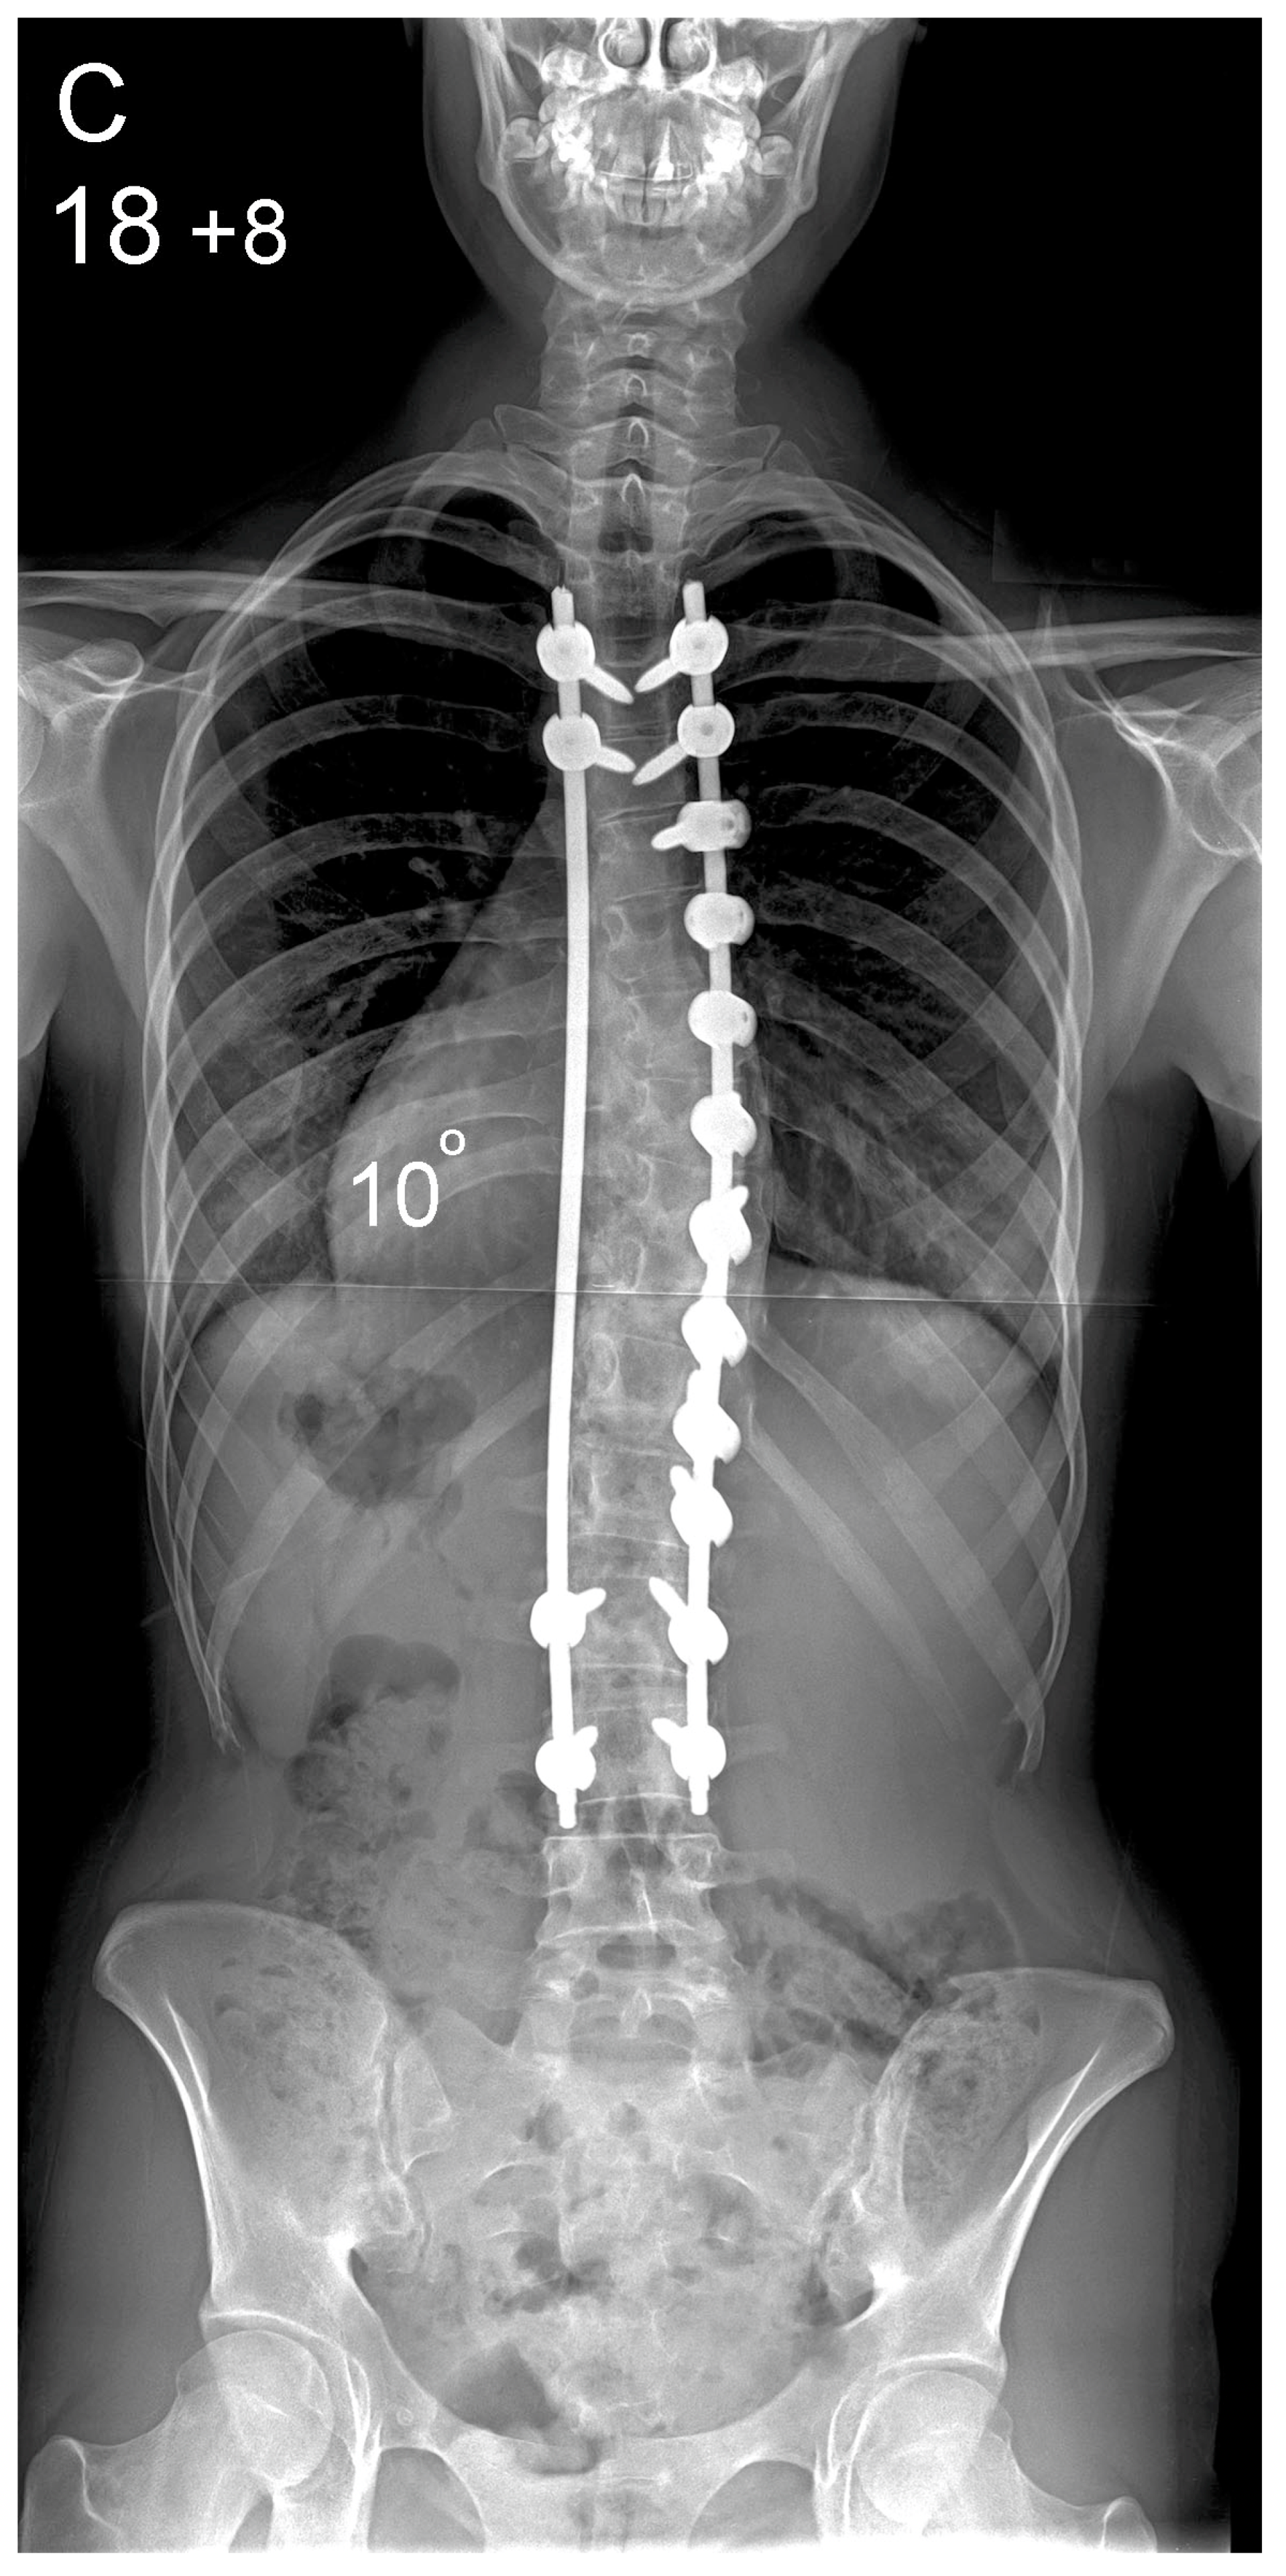

Figure 1.

Patient aged 15 years and 9 months with a right thoracic AIS producing thoracic translocation and listing of the trunk to the right, as well as thoracic flat back producing negative global sagittal balance of the spine and compensatory cervical kyphosis (A,B). The patient underwent posterior scoliosis correction using the AS technique which restored segmental and global coronal/sagittal spinal balance at latest follow-up (age 18 years and 8 months) into adult life (C,D). Clinical photographs demonstrate excellent correction of the coronal deformity and associated rib hump after scoliosis surgery (E–H).